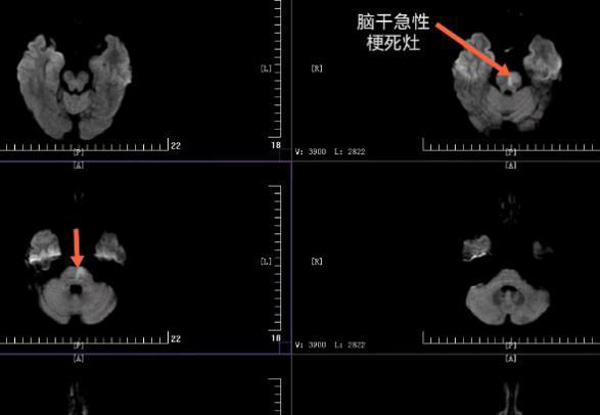

4月23日11时55分,陕健医二一五医院神经内科二病区收到一位33岁的男性患者,言语不清,轻度躁动,右侧肢体无力,间断有意识障碍发作。磁共振显示:患者桥脑左侧半切状梗死,同时合并小脑多发点片状梗死。基底动脉中段重度狭窄,随时有生命危险。

随着3枚支架由远及近依次顺利植入,血流终于完全恢复,患者总算转危为安了。术后24小时,患者症状逐渐减轻,语言肢体功能完全恢复,终于可以回归正常生活。

脑干梗死是非常危重的一种疾病,预后很差,患者重残及死亡的比例高达70%,所以一旦发生这种情况,必须尽早到医院抢救治疗,才能增加挽救生命,减少残疾等后遗症的可能性。二一五医院目前是国家级高级卒中中心,常年开展急性脑梗死的溶栓、取栓工作,有着经验丰富的医疗团队,是咸阳市最早开展介入取栓手术的医院之一。脑梗死一旦发病,溶栓取栓的时间窗非常短暂,所以要争分夺秒,尽早开展抢救工作,二一五医院7×24小时开展脑卒中的抢救工作,守护广大群众的健康。